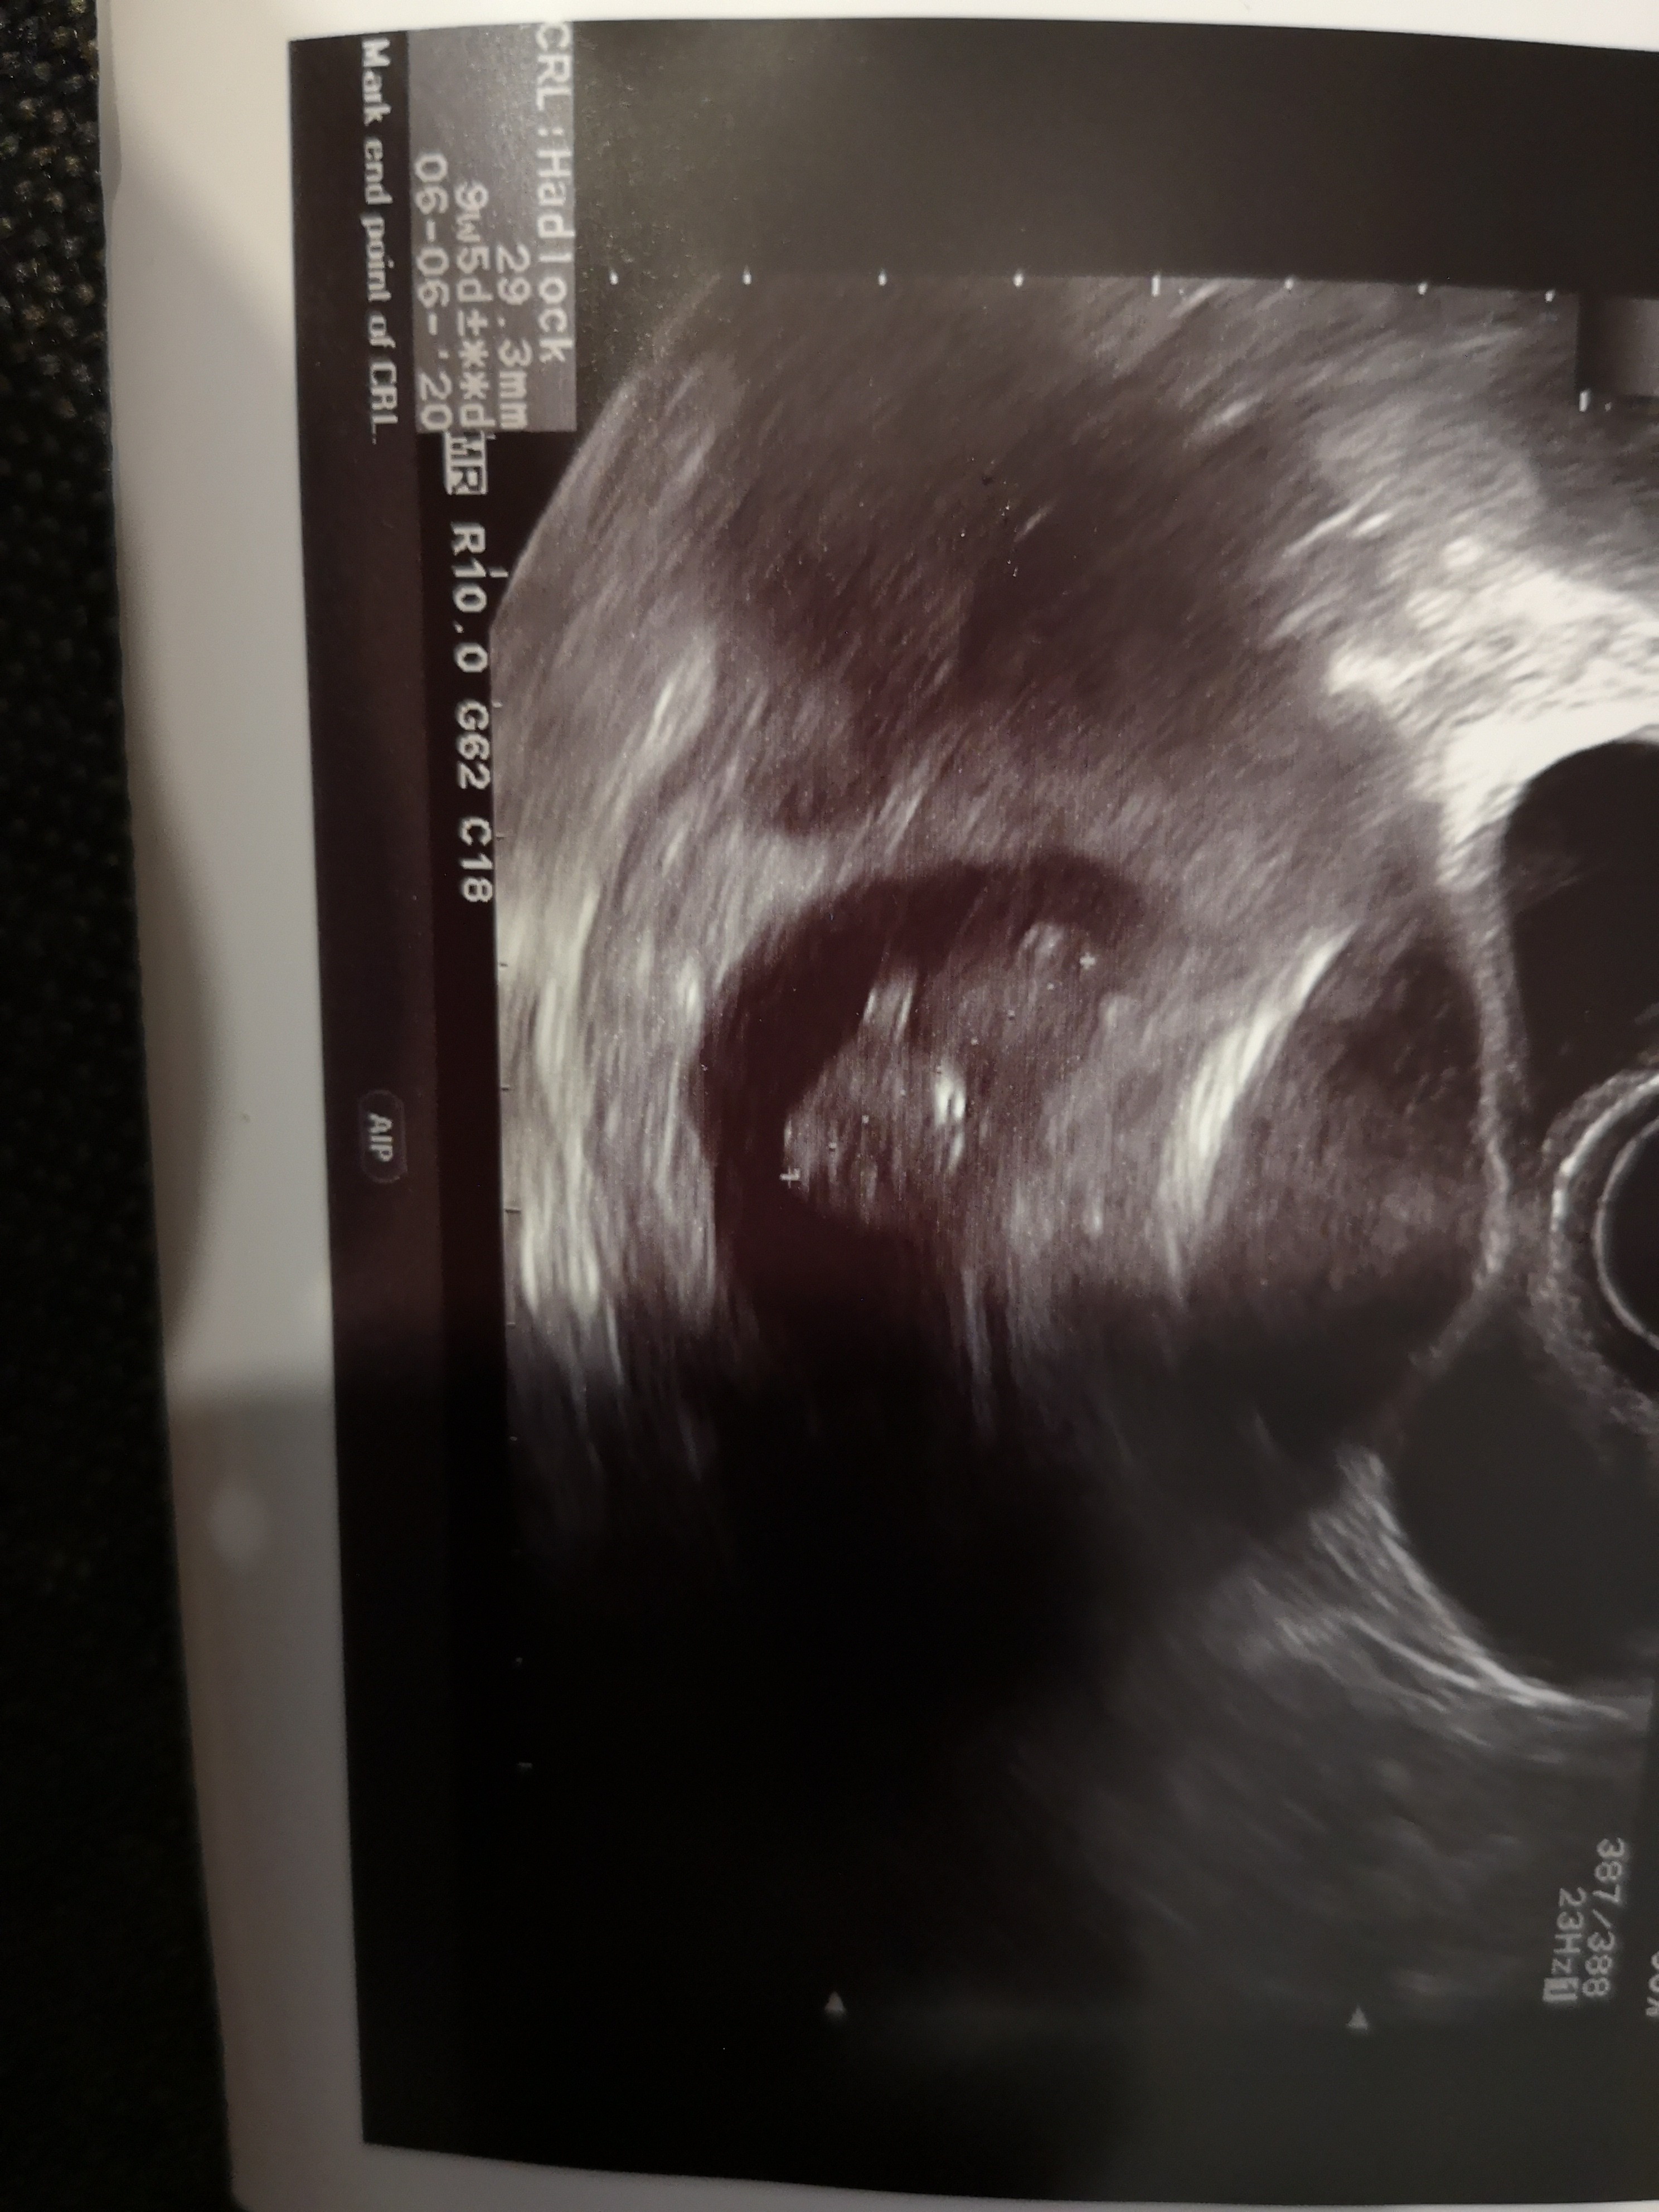

Extra ! GratulacjeNa szczęście jak do tej pory wszystko jest ok, uhh Dodaje dzisiejsze zdj bobo

9+5Extra ! Gratulacjektóry to tydzień teraz ?